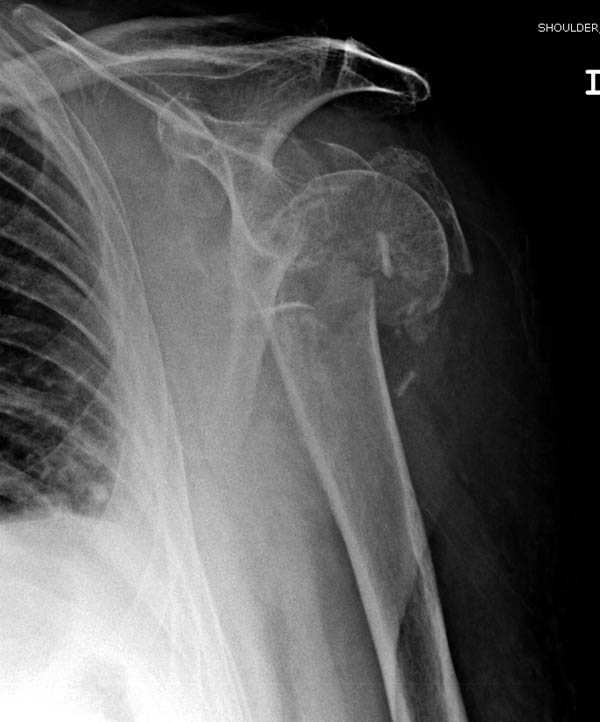

дополнительные снимки по протезированию